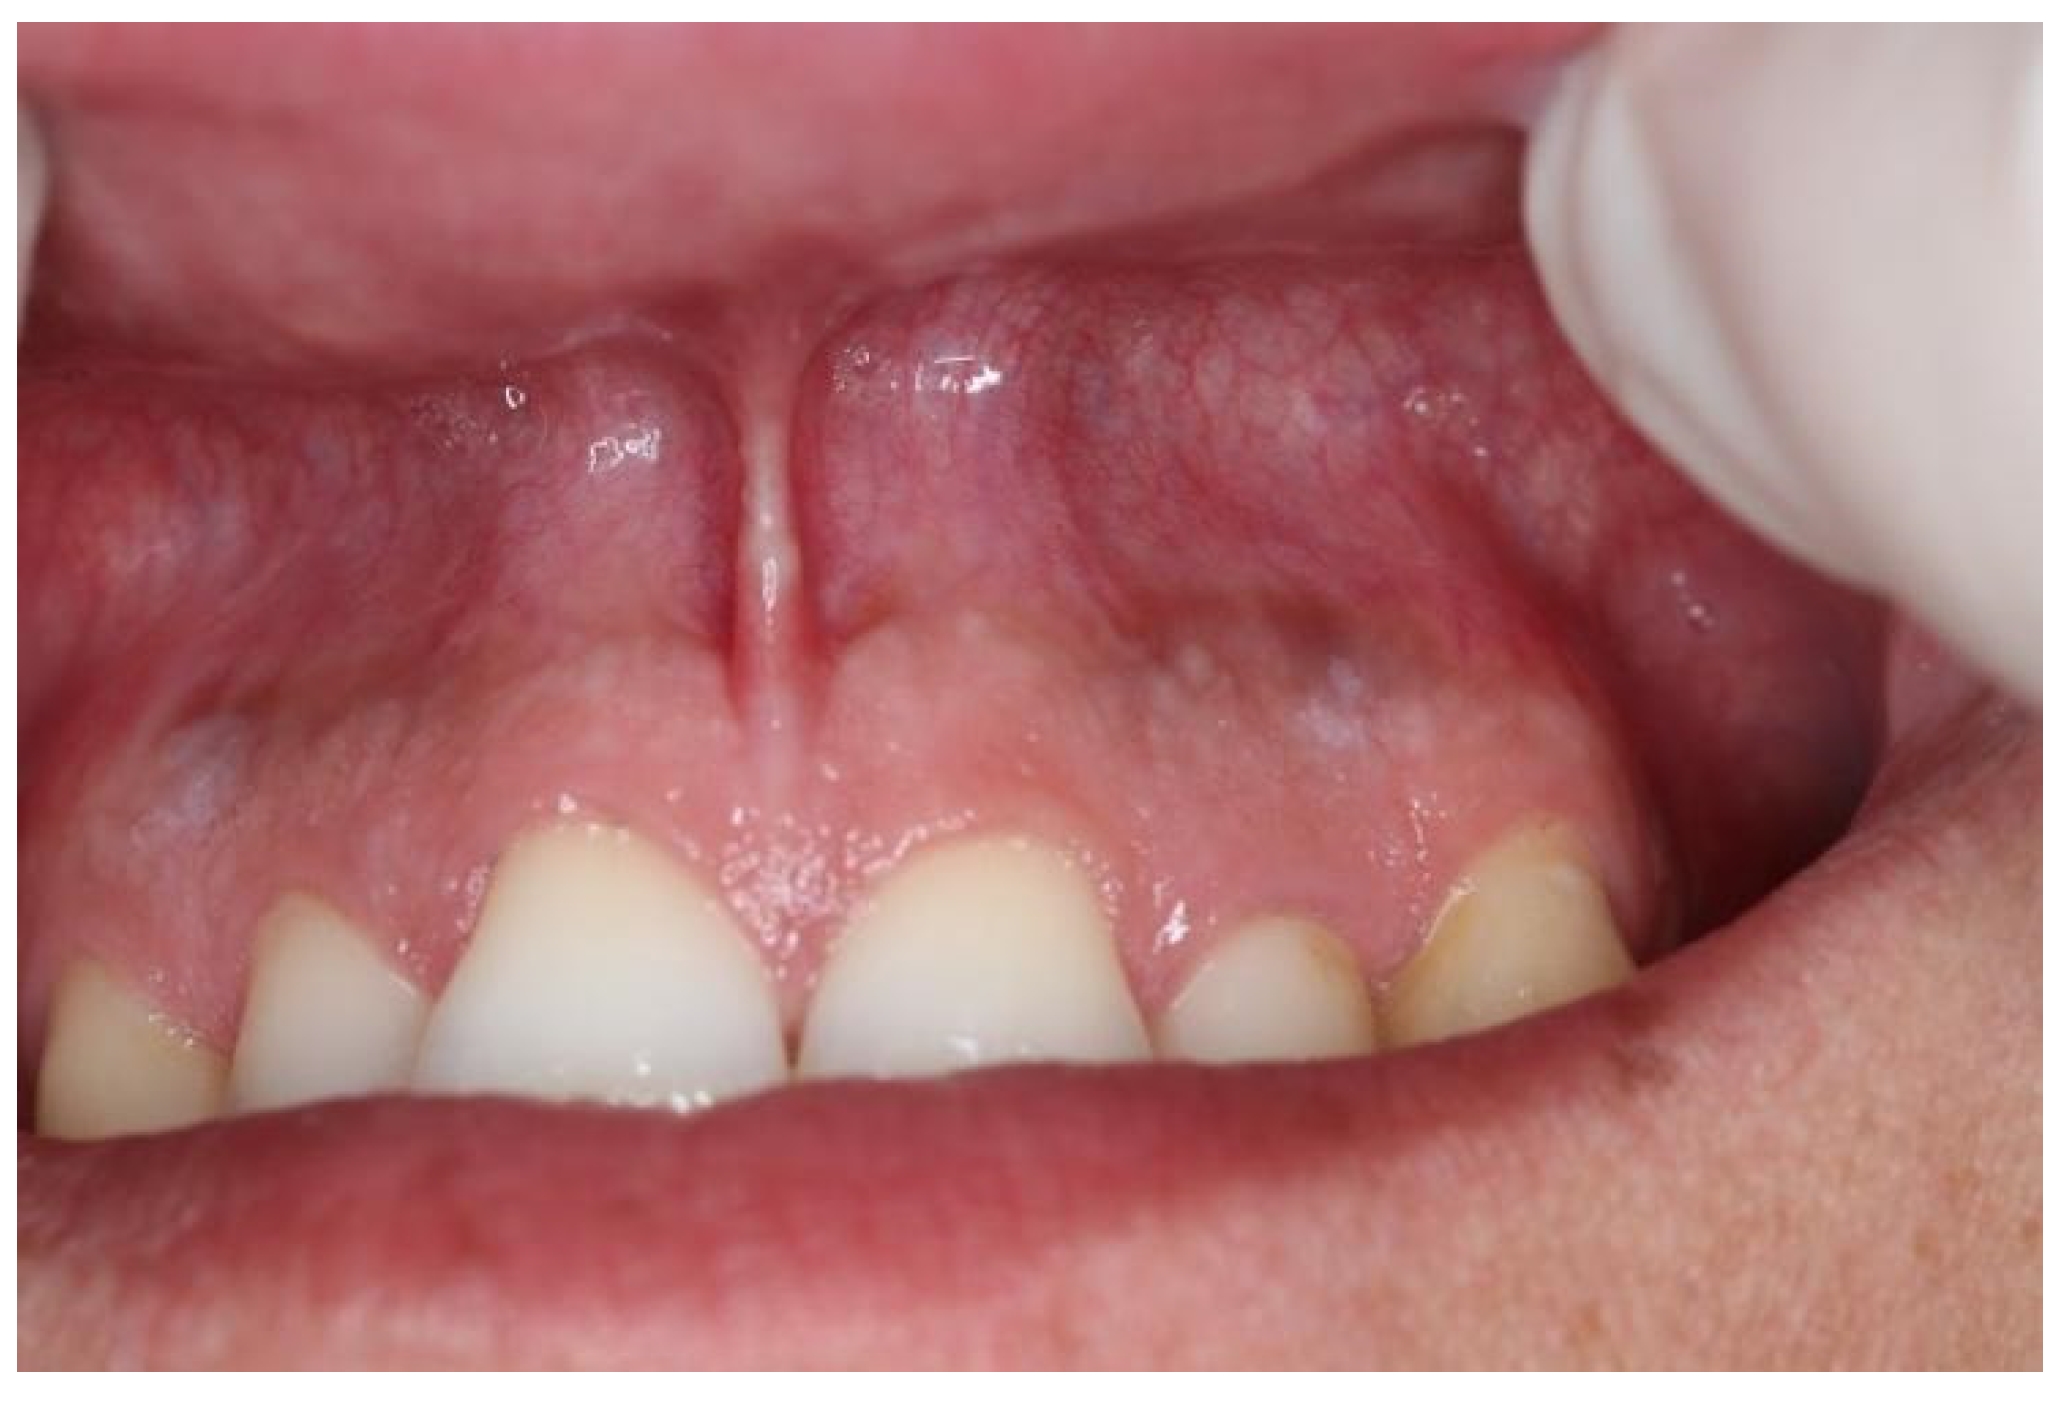

| Snus | 5–10 | 2–5 | White round lesion (Figure 2) | Above tooth nr. 13, 12 |